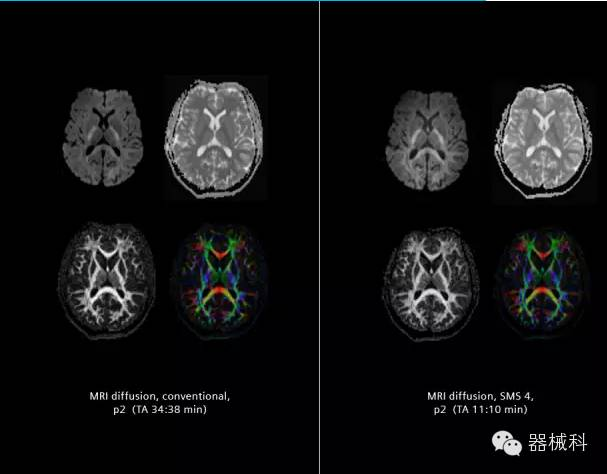

在2015年RSNA上,西門子隆重發(fā)布了Simultaneous Multi-slices 技術(shù)(即同時多層采集技術(shù),簡稱SMS),這是磁共振掃描技術(shù)中第一次引入“同時多層”的概念,此概念技術(shù)的發(fā)布,將對未來磁共振成像領(lǐng)域帶來巨大的變革!

擁有了SMS“同時多層”采集技術(shù)之后,用戶可以在非常短的時間內(nèi)完成MR掃描,結(jié)合西門子靜音技術(shù),大大提高患者的舒適性,或在單位時間內(nèi)采集更多的數(shù)據(jù),也可以得到高精度、高準(zhǔn)確性、大數(shù)量的功能成像數(shù)據(jù),為臨床和科研提供強大的支持。專家認(rèn)為,SMS“同時多層”采集技術(shù)未來在 提高成像質(zhì)量、外科手術(shù)計劃、降低術(shù)后神經(jīng)功能缺陷、提高fMRI的時間采集效率、提高靜息態(tài)功能磁共振數(shù)據(jù)質(zhì)量等方面將帶來深遠(yuǎn)影響,希望該技術(shù)可以盡早面世,引領(lǐng)磁共振進入多層時代!